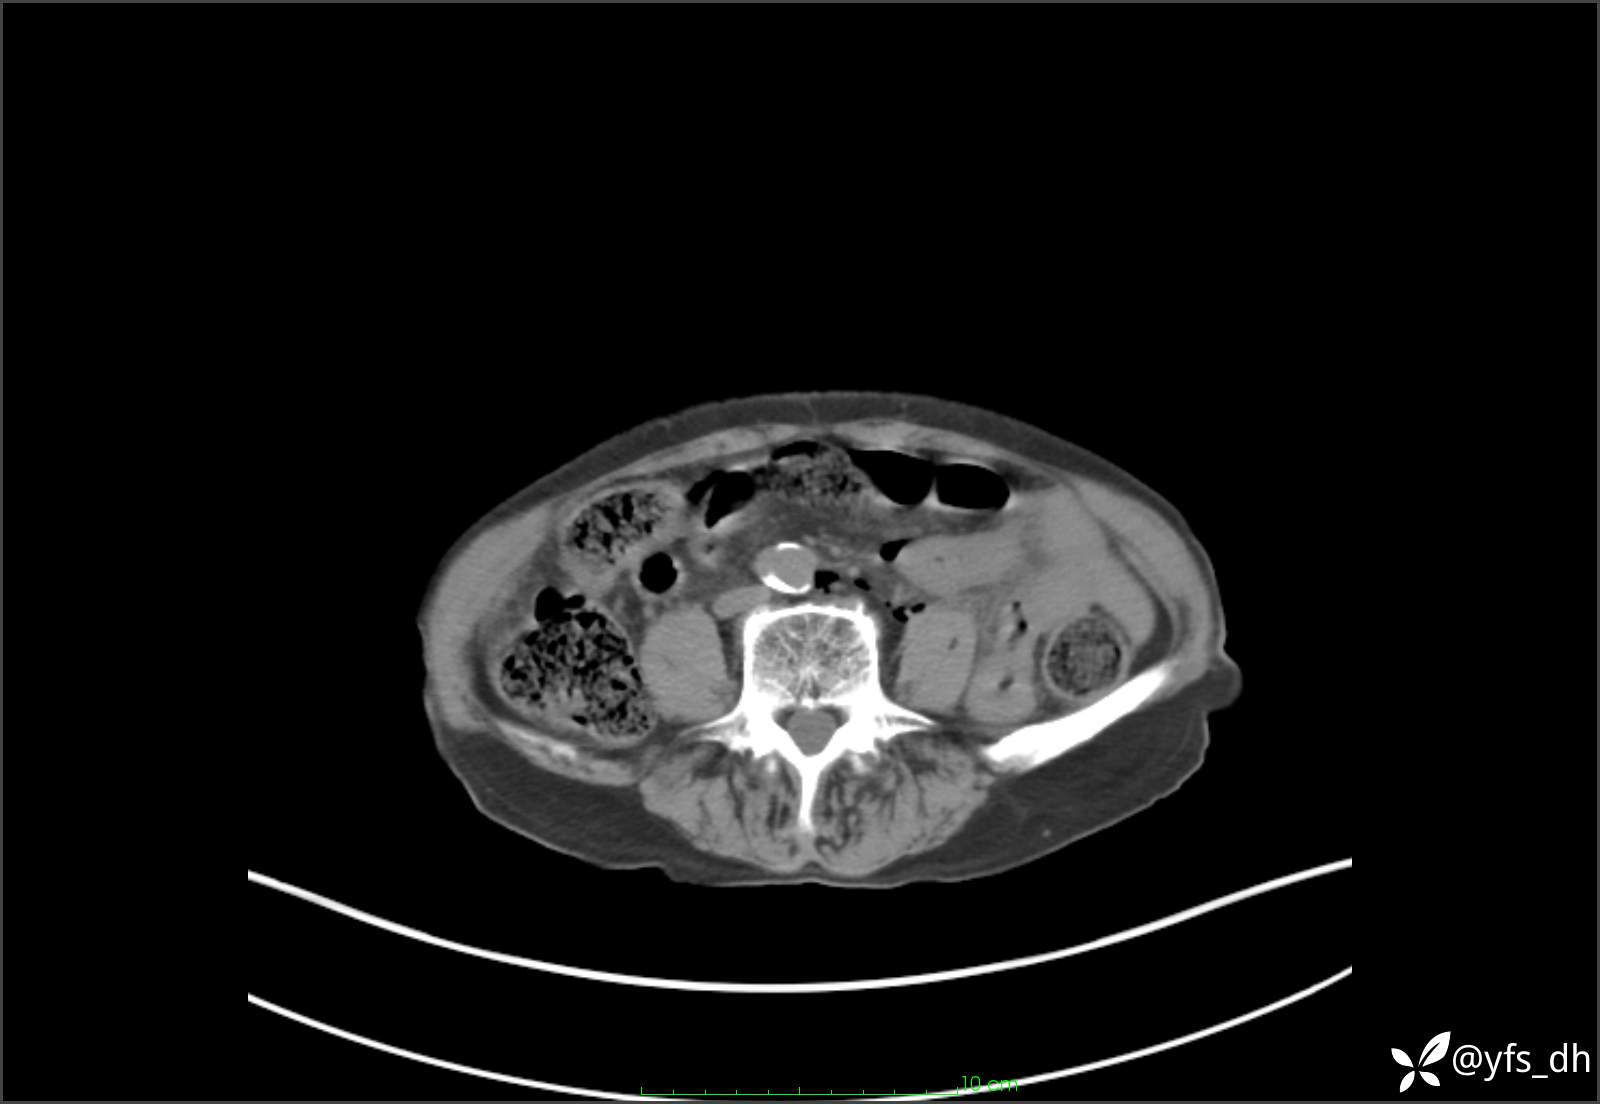

1.简要病史:患者4天前突发上腹部疼痛不适,但可以忍受。3小时前饭后突然加重,不能忍受后就诊。

2.简要手术记录:术中见腹盆腔大量肠液及粪便,乙状结肠中下段见一约3cm的破口。